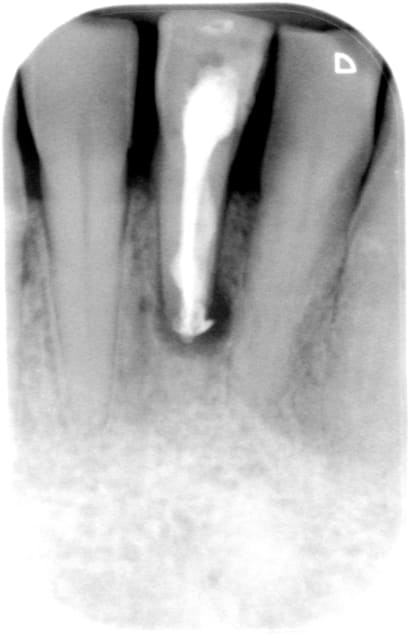

la suite pour blette que ça interesse .je suis agréablement surpris de la de la rétention et de la stabilité données par cs 2 pins dentinaires

photos lundi ou mardi scellé